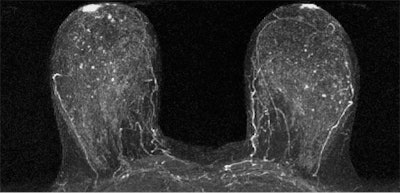

Contrast enhancement of normal tissue on breast MRI scans is more effective than tissue density as an imaging biomarker of breast cancer and could make existing risk models more accurate, according to a new study published online May 12 in Radiology.

Researchers from the University of Washington found that women with an MRI assessment of mild, moderate, or marked background parenchymal enhancement (BPE) were nine times more likely to develop breast cancer than women with minimal BPE. In contrast, tissue density measured by both MR and mammography was not a statistically significant indicator.

BPE, however, was significantly linked to cancer: The women with mild, moderate, or marked background parenchymal enhancement made up the majority of the cancer cohort.

"We found that a significantly higher percentage of women in the cancer cohort had either mild, moderate, or marked BPE (78%) than did women in the control cohort (43%)," the authors wrote.

The results suggest that qualitative MRI assessment of BPE may be useful for predicting breast cancer risk -- even more so than MR assessment of fibroglandular tissue or mammographic assessment of density, the researchers concluded. And if the results are confirmed by larger studies, integrating BPE into breast cancer risk assessment tools could help customize options for individual women, according to Rahbar.